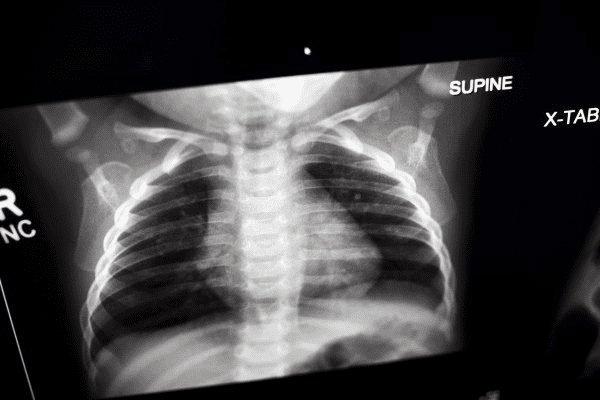

An X-ray is a picture of the inside of your child’s body and is the most frequently used form of medical imaging. An X-ray is an actual form of energy that passes through the body on to a recording plate that creates the image. X-rays are used to take still pictures of the bones and organs in the body. X-rays are painless, fast, and easy to get. At CHOC, your child will receive a high-quality and rapid X-ray examination using the lowest radiation dose possible and proudly follow the Image Gently campaign.

- Chest x-ray – can help doctors find the cause of a cough, shortness of breath, or chest pain. It can detect signs of pneumonia, a collapsed lung, heart problems (such as a enlarged heart), and broken ribs or lung damage after injury. Learn more about chest X-rays.